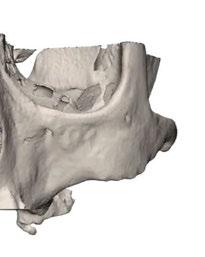

Este caso clínico es un premolar que tiene 3 conductos: sabemos que 2 de ellos son en la raíz vestibular, y

Figura 8. Secuencia operatoria en casos de extrema dificultad instrumental. Figura 9. Recomendación secuencial del tipo de movimiento, dependiendo de la dificultad instrumental del conducto.

39 Gaceta Dental · N o 365 | Abril 2024 Caso clínico. CIENCIA Y CLÍNICA

en el CBCT podemos apreciar a qué longitud del conducto se produce la bifurcación (Figura 10)

Debido a la gran curvatura que se produce en la bifurcación, tenemos que precurvar los instrumentos manuales y rotatorios, para facilitar que los instrumentos alcancen la LT (Figura 11). Terminamos el conducto mesiovestibular y palatino en conicidad .06 y el disto-vestibular en .04 debido al riesgo que pensamos que correríamos si hacemos una secuencia más amplia.

Valorando cada uno de los factores que hemos descrito anteriormente, podemos decidir, para el éxito de este tratamiento, una combinación: secuencia más progresiva; trabajar 3 ciclos por conducto para los instrumentos de preinstrumentación y conformación; eliminación de interferencias coronales con puntas ultrasónicas

e instrumento 25.09; terminar en conicidad .04/.06 según la dificultad del conducto; combinar movimiento continuo y alterno; y usar instrumentos precurvados de manera manual previo al rotatorio. Todo esto hará que resolvamos este caso clínico de manera satisfactoria (Figura 12). ●